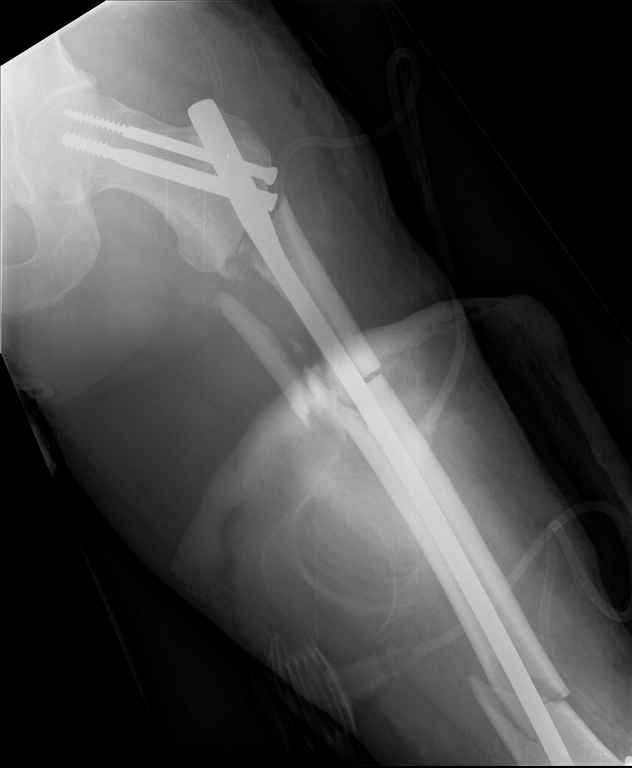

Неделю назад поступил пациент после ДТП. В тяжелом

состоянии. Ds: ТСТ. ЗЧМТ. СГМ. ЗТГК. О/фрагментарный перелом левого бедра. З/оскольчатый

перелом с\3 левого плеча. Перелом левого локтевого отростка. З/перелом наружного мыщелка

б/берцовой кости в/3 м/берцовой кости левой голени. при поступлении, ПХО раны левого бедра(

рана 1х1см по наружной поверхности бедра в с/3) налажено скелетное вытяжение , и гипсовая

лонгета на левую в/конечность.Находился в реанимации.

17.02.11был прооперирован: БИОС левого плеча, о/синтез левого

локтевого отростка по Веберу, БИОС левого бедра( длинная

версия Fi-Can Sanatmetal диаметр 10мм), мыщелок голени трогать не стали.при остеосинтезе

бедра возникли трудности при закрытй репозиции перелома в н/3, в связи с чем решили открыться

внизу , отрепонировали без особого труда и выполнили блокирование во фронтальной плоскости

3-мя винтами + 1 винт спереди гвоздя( промазал). Убрал костодержатель, все нормально,

контроль ЭОПом стояние отломков нормальное, зашились. На контрольной R-мме на утро

выявлено вторичное смещение дистального отломка. Левая нога по сравнению со здоровой

удлиннена до 2,5см( это за счет вальгусной установки гвоздя в проксимальном отделе, боялся

свалиться на варус).